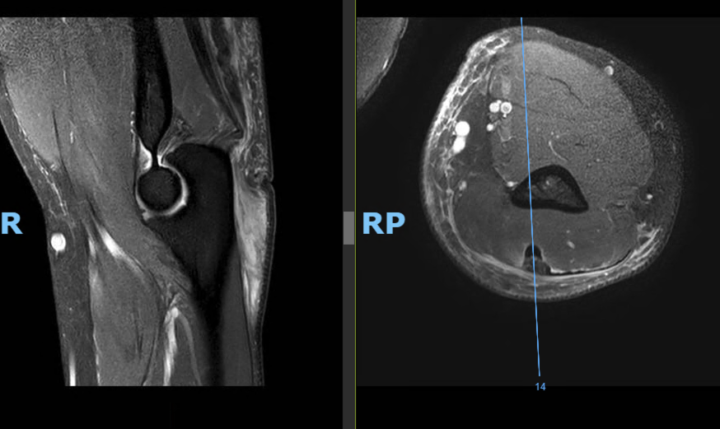

The femoral plasty screw protrudes 15 mm from the posterior femoral cortex. Is this normal or can it cause symptoms? Thanks! https://www.cmrad.com/cases/1711855257

https://www.cmrad.com/cases/1711855257